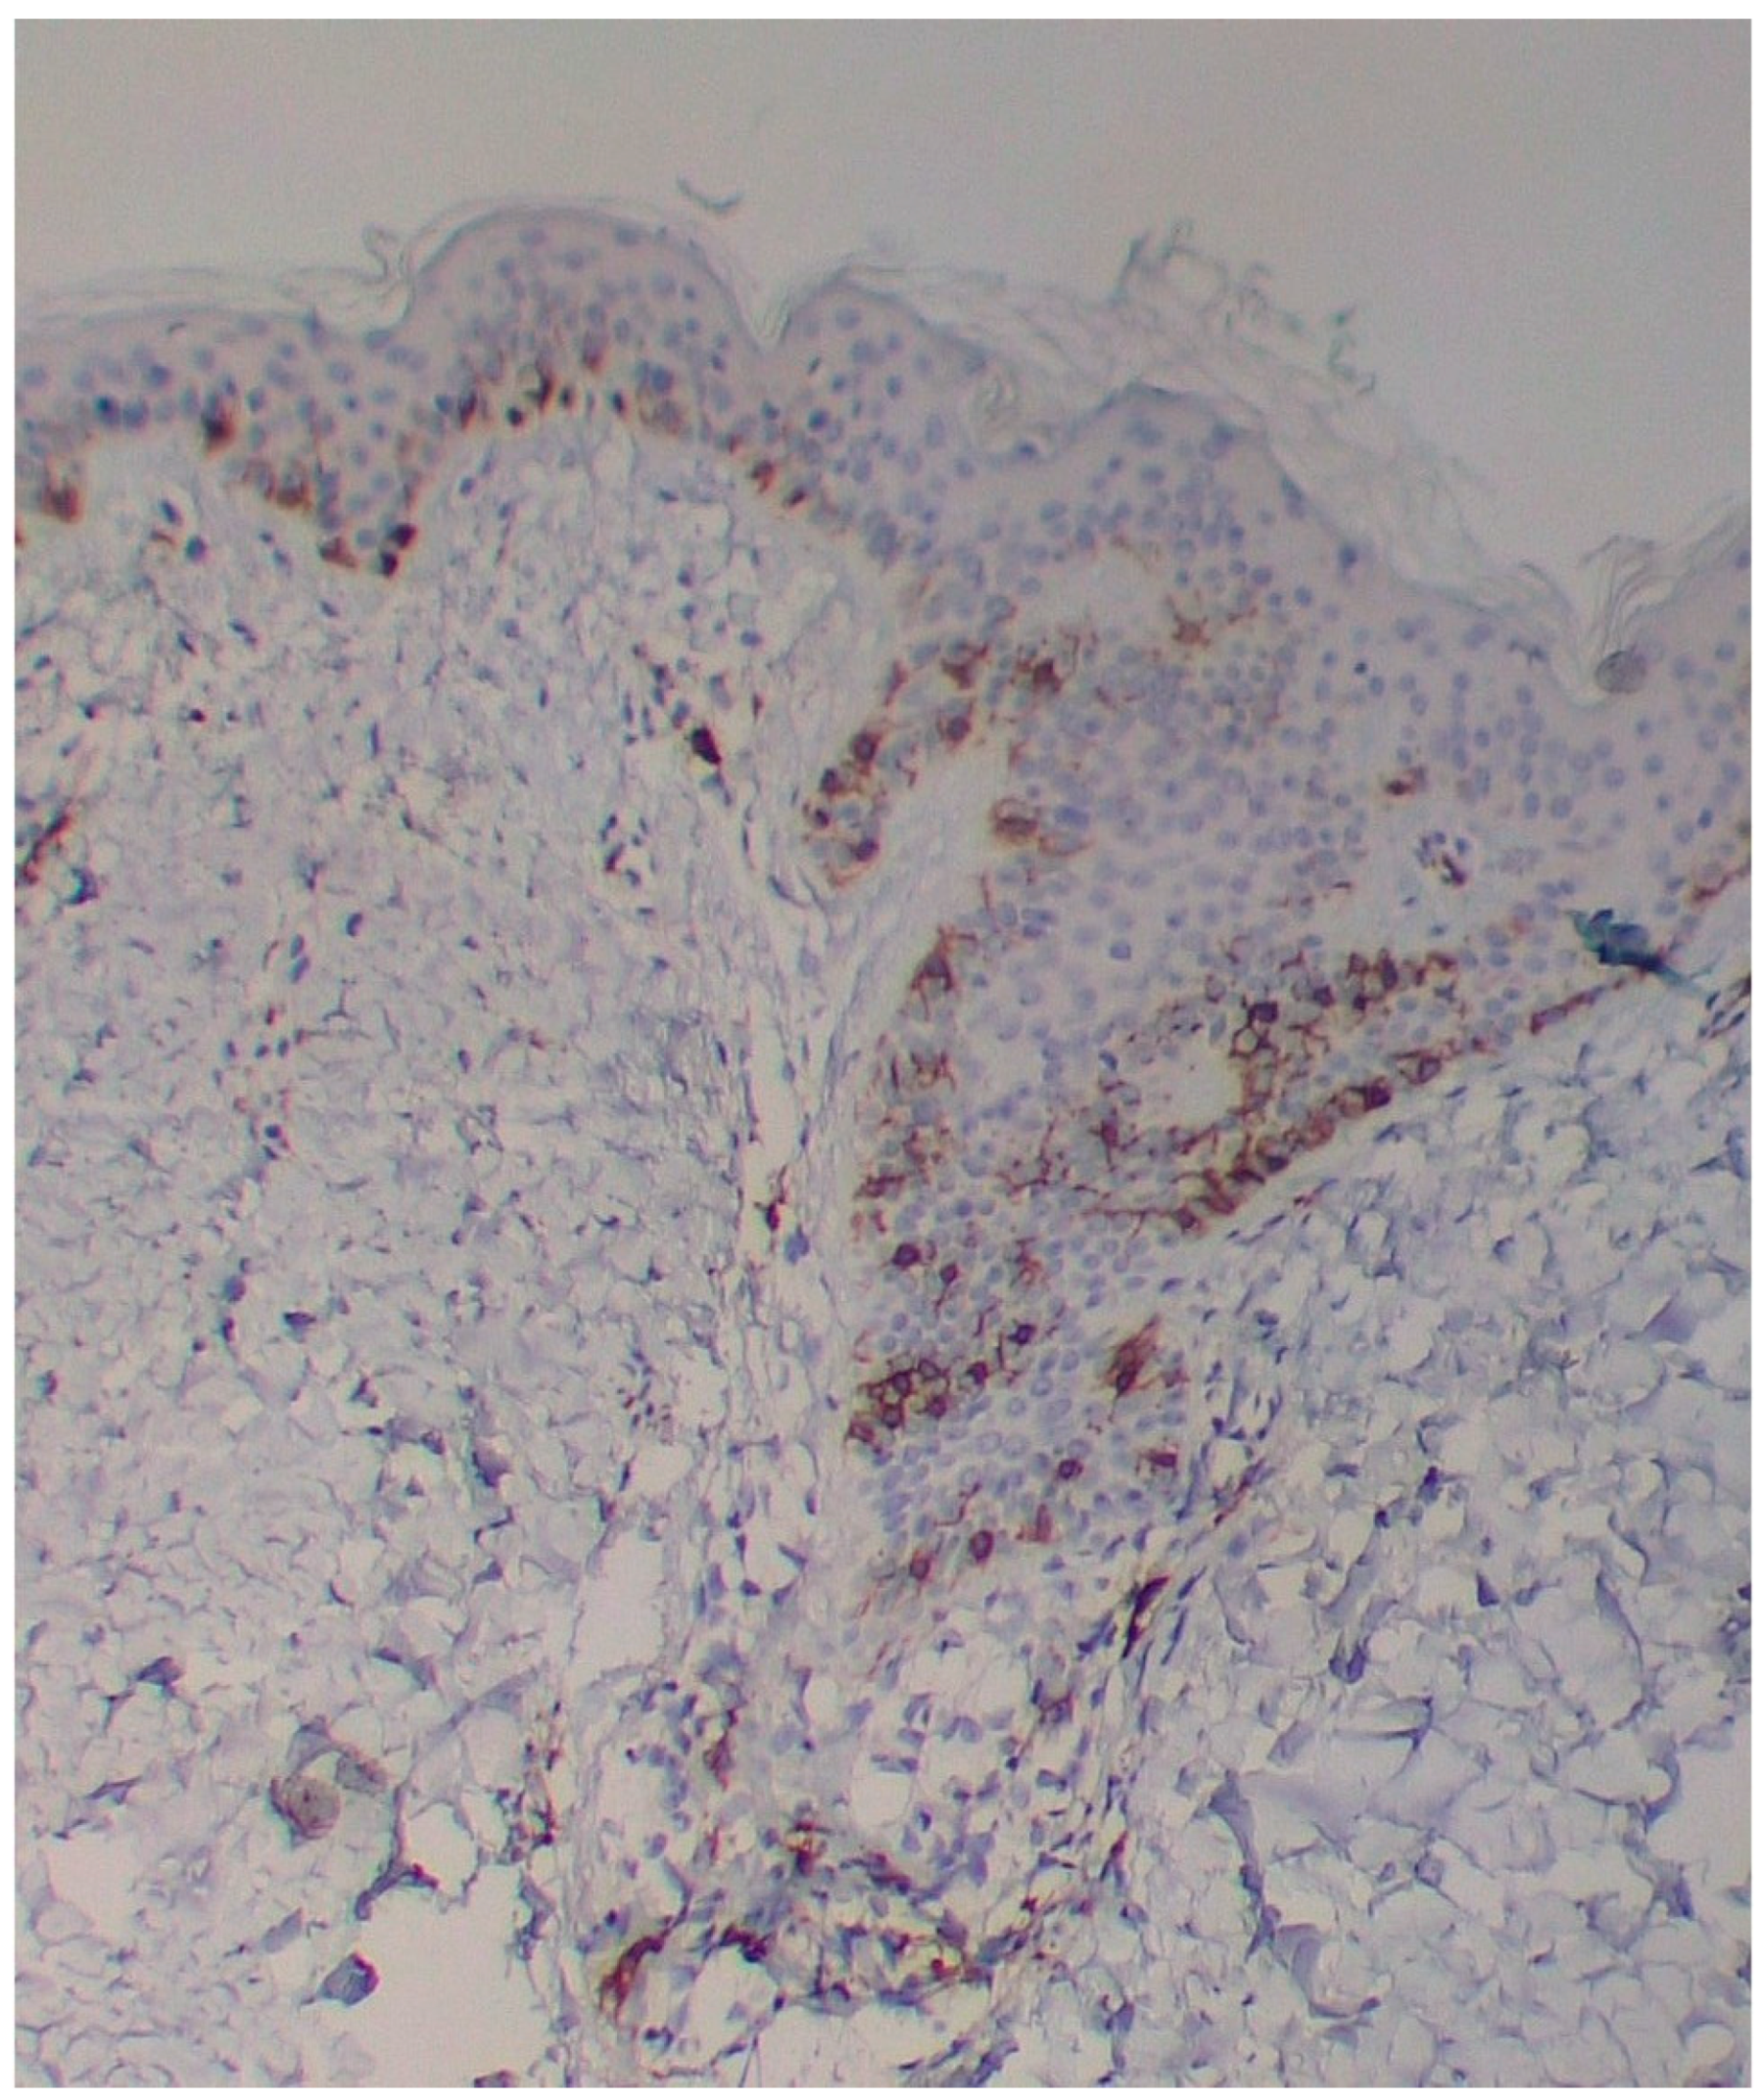

A skin biopsy showed basal cell hyperpigmentation and a chronic superficial perivascular inflammatory infiltrate that also affected the periphery of the hair follicles (Figure 6). Tryptase stain reached figures of up to 29 mast cells per high-power view (67/mm2), and CD117 up to 46 mast cells per high-power view (92/mm2), mostly surrounding the hair infundibulum (Figure 7), although some interstitial mast cells were also observed (Figure 8). PAS stain was negative for yeasts or fungal hyphae. Abdominal ultrasound study did not detect any anomalies. The bone scintigram detected mild non-specific osteoblastic lesions in the L5, S1 and sacroiliac joints (pending further study).

Figure 6. Basal cell pigmentation and superficial dermal inflammatory infiltrate, mostly surrounding the pilosebaceous infundibulum (HE ×40).

Figure 7. Mast cell infiltration in superficial dermis and around a pilosebaceous follicle (CD117 ×100).